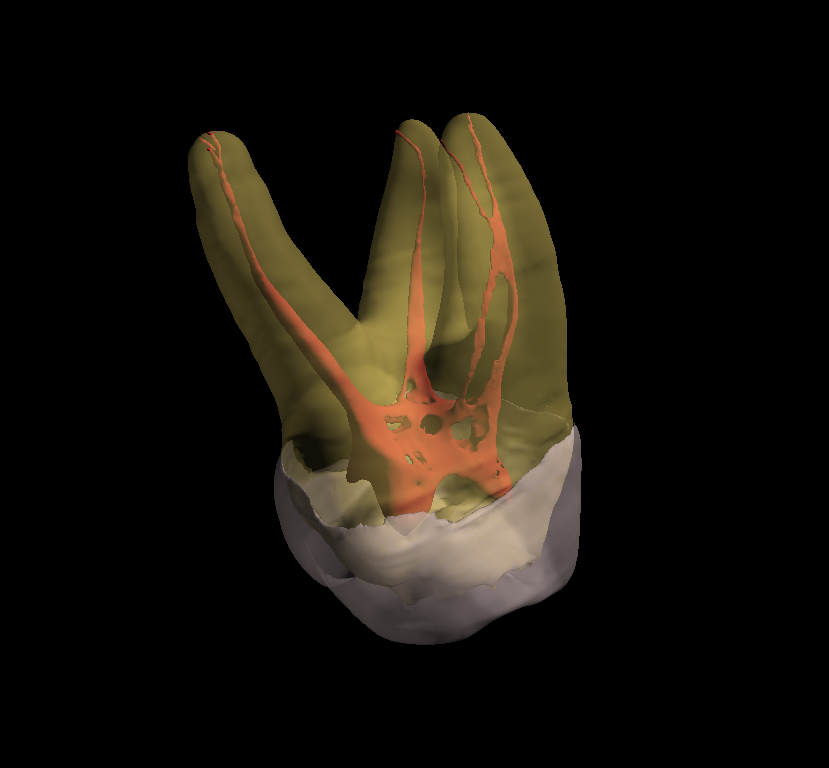

Conventional intra-oral radiography provides clinicians with cost-effective, high-resolution imaging that continues to be the front-line method for dental imaging. However, it is clear that there are many specific situations where the 3-D images produced by CBCT facilitates diagnosis and influences treatment. The usefulness of the CBCT cannot be disputed. It is a valuable task-specific imaging modality, producing minimal radiation exposure to the patient and providing maximal information to the clinician.